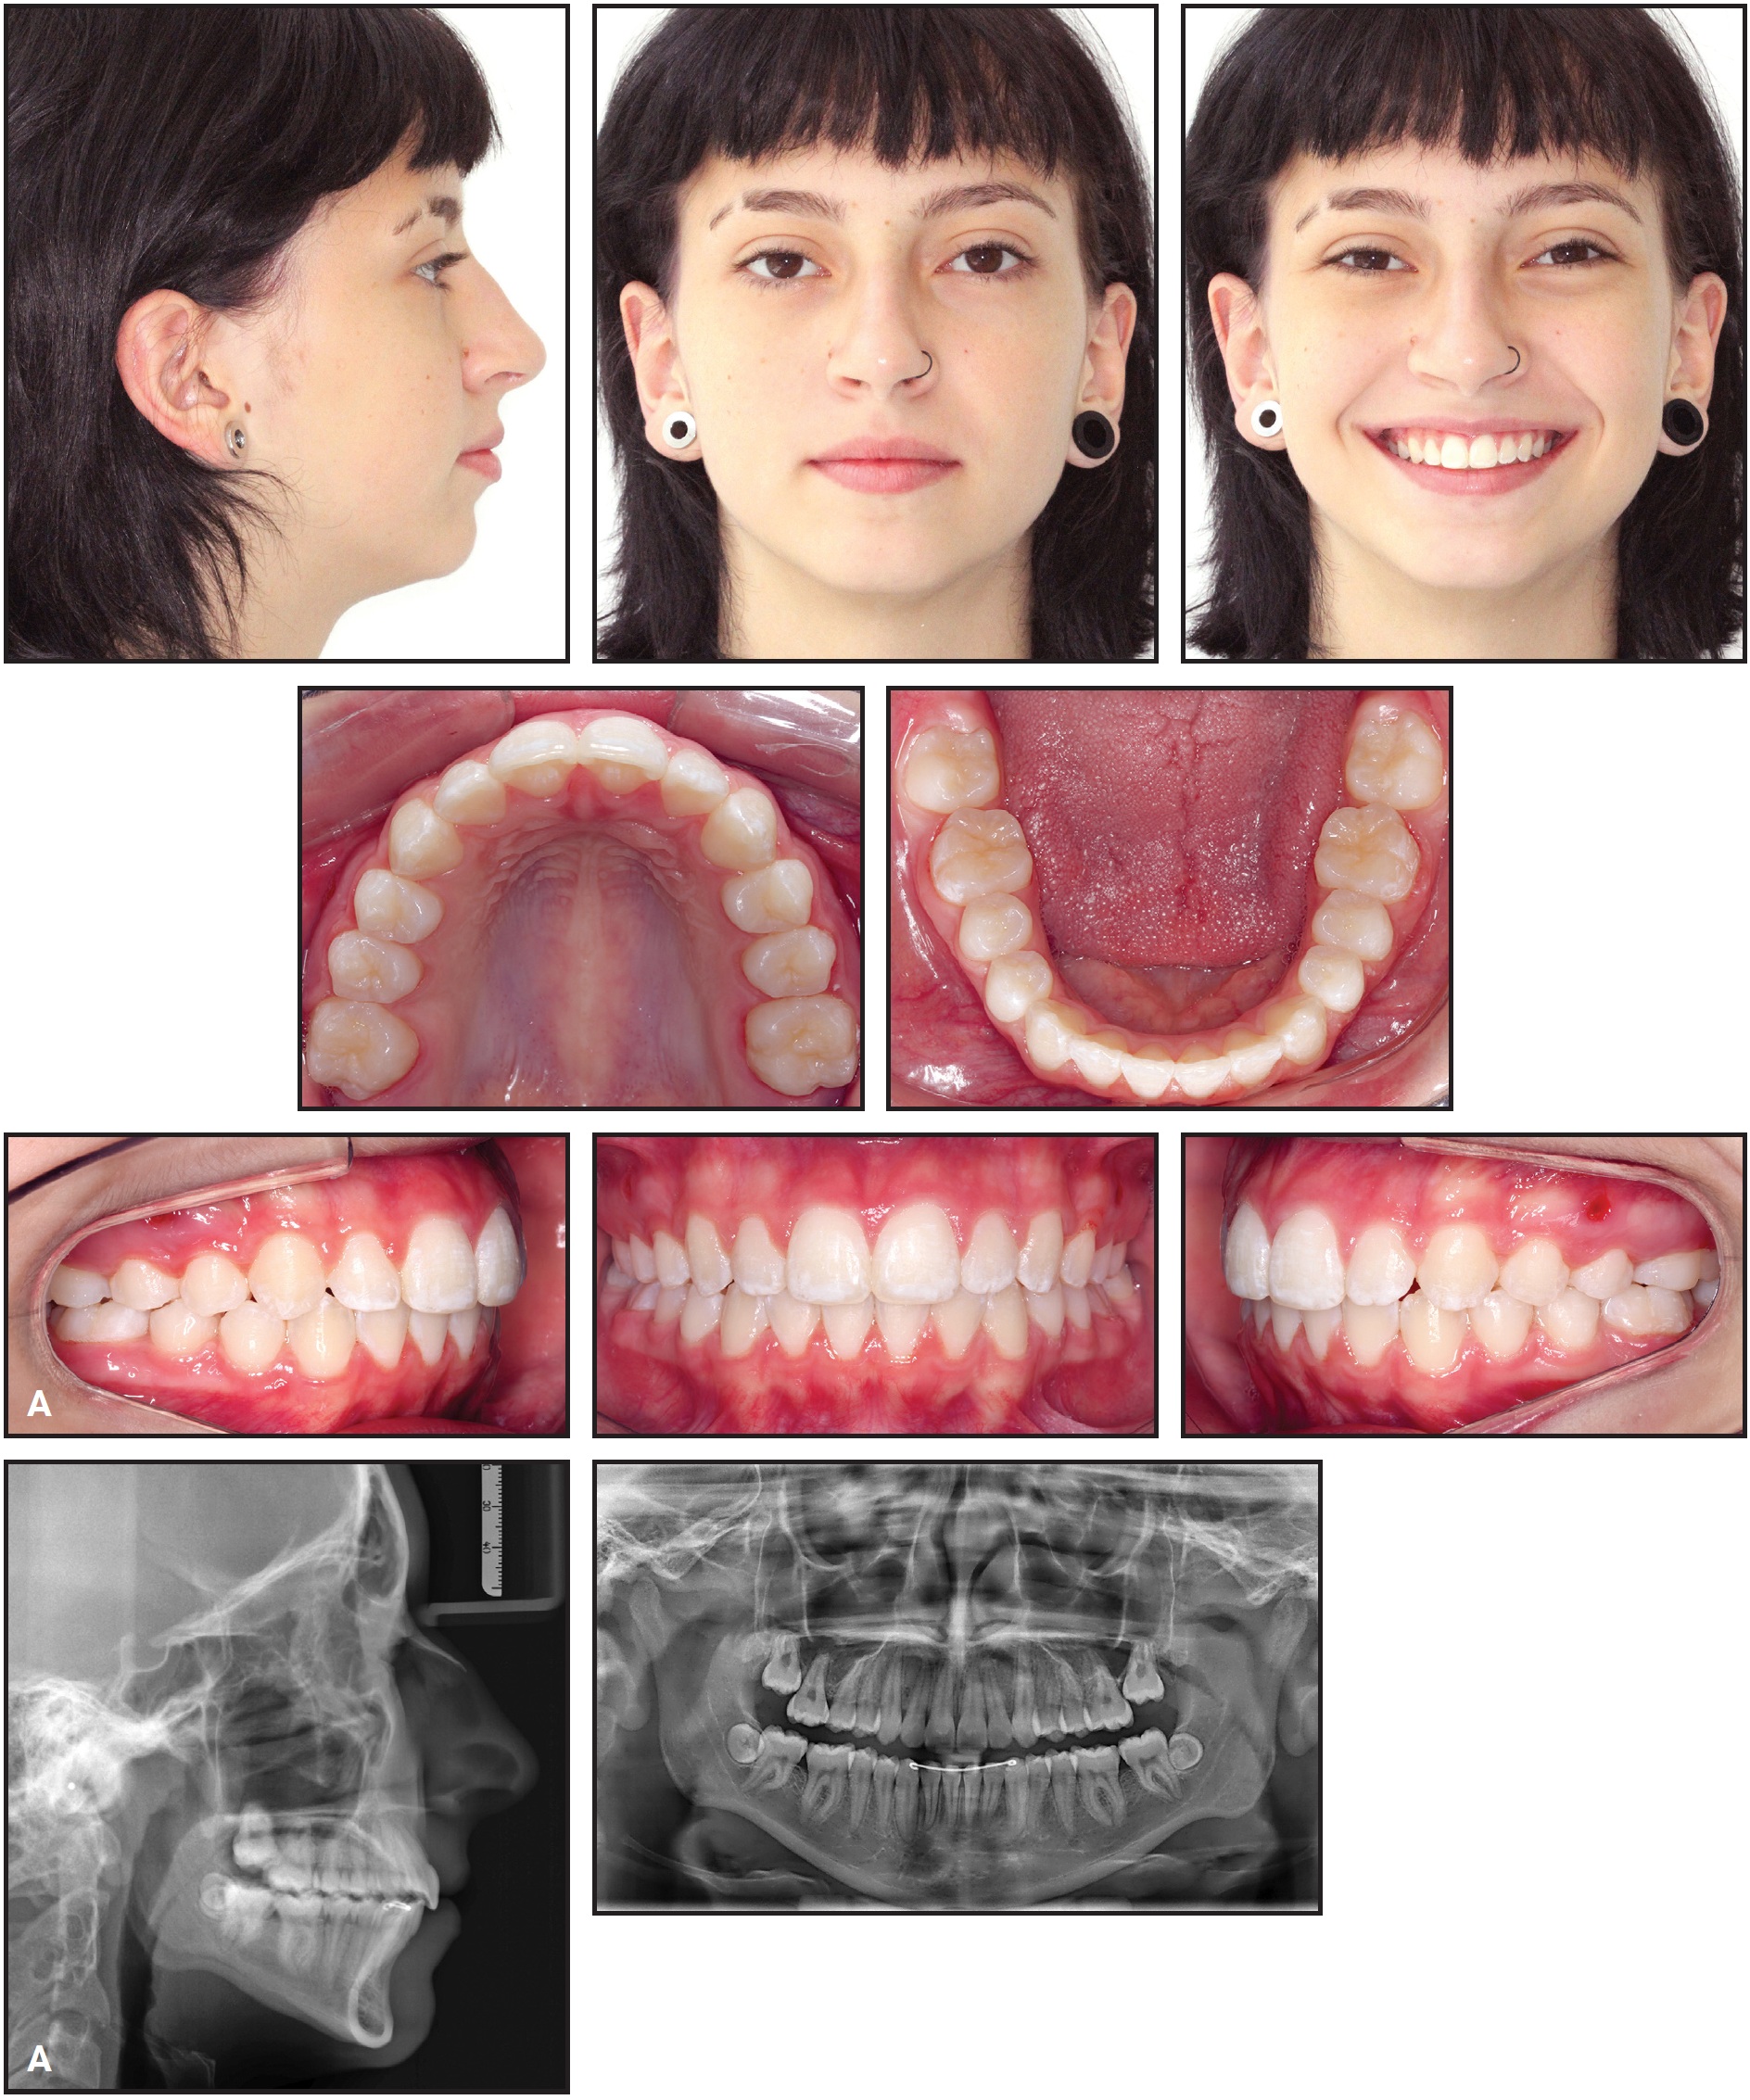

Total treatment time was 13 months (Fig. 11A).

Fig. 11 A. Patient after 13 months of treatment (continued in next image).

Excellent smile esthetics and a static and functional occlusion were obtained. The upper incisors were extruded and palatally tipped, while the upper molars were intruded. The occlusal plane underwent clockwise rotation, and the upper posterior teeth were uprighted. Consequently, the anterior open bite was closed, the overbite was overcorrected, and occlusal contact was established between the premolars. The Class I molar relationship and the posterior transverse relationship were maintained. The lower incisors were protruded to resolve the anterior crowding. External apical root resorption involved no more than slight rounding, which is considered clinically acceptable.39 The upper second molars were erupting toward the occlusal plane, but the left second molar showed a less favorable eruption axis; therefore, the patient was kept under observation to evaluate whether surgical intervention would be required (Fig. 11B).

Fig. 11 (cont.) A. Patient after 13 months of treatment. B. Superimposition of pretreatment (black) and post-treatment (red) cephalometric tracings.